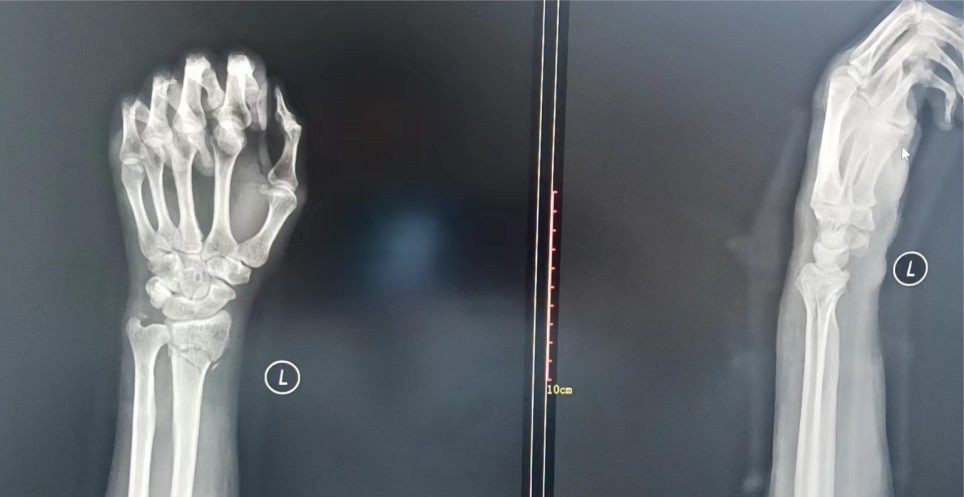

开始工作的第一周,骨科收治了一名桡骨远端骨折患者。男性,42岁,是家里唯一的“顶梁柱”,可是家庭条件并不富裕。韩建明主任仔细查看患者影像学检查资料后,结合患者经济状况,针对性地制定了压垫和小夹板结合的保守治疗方案。

经过韩主任短短数分钟的牵拉及手法复位,纠正了患者的腕部畸形,局部血肿逐渐消散。

第二天复查X光片,治疗效果满意,韩主任耐心叮嘱其出院后注意事项,嘱咐定期门诊复查,患者及家属连连感谢。